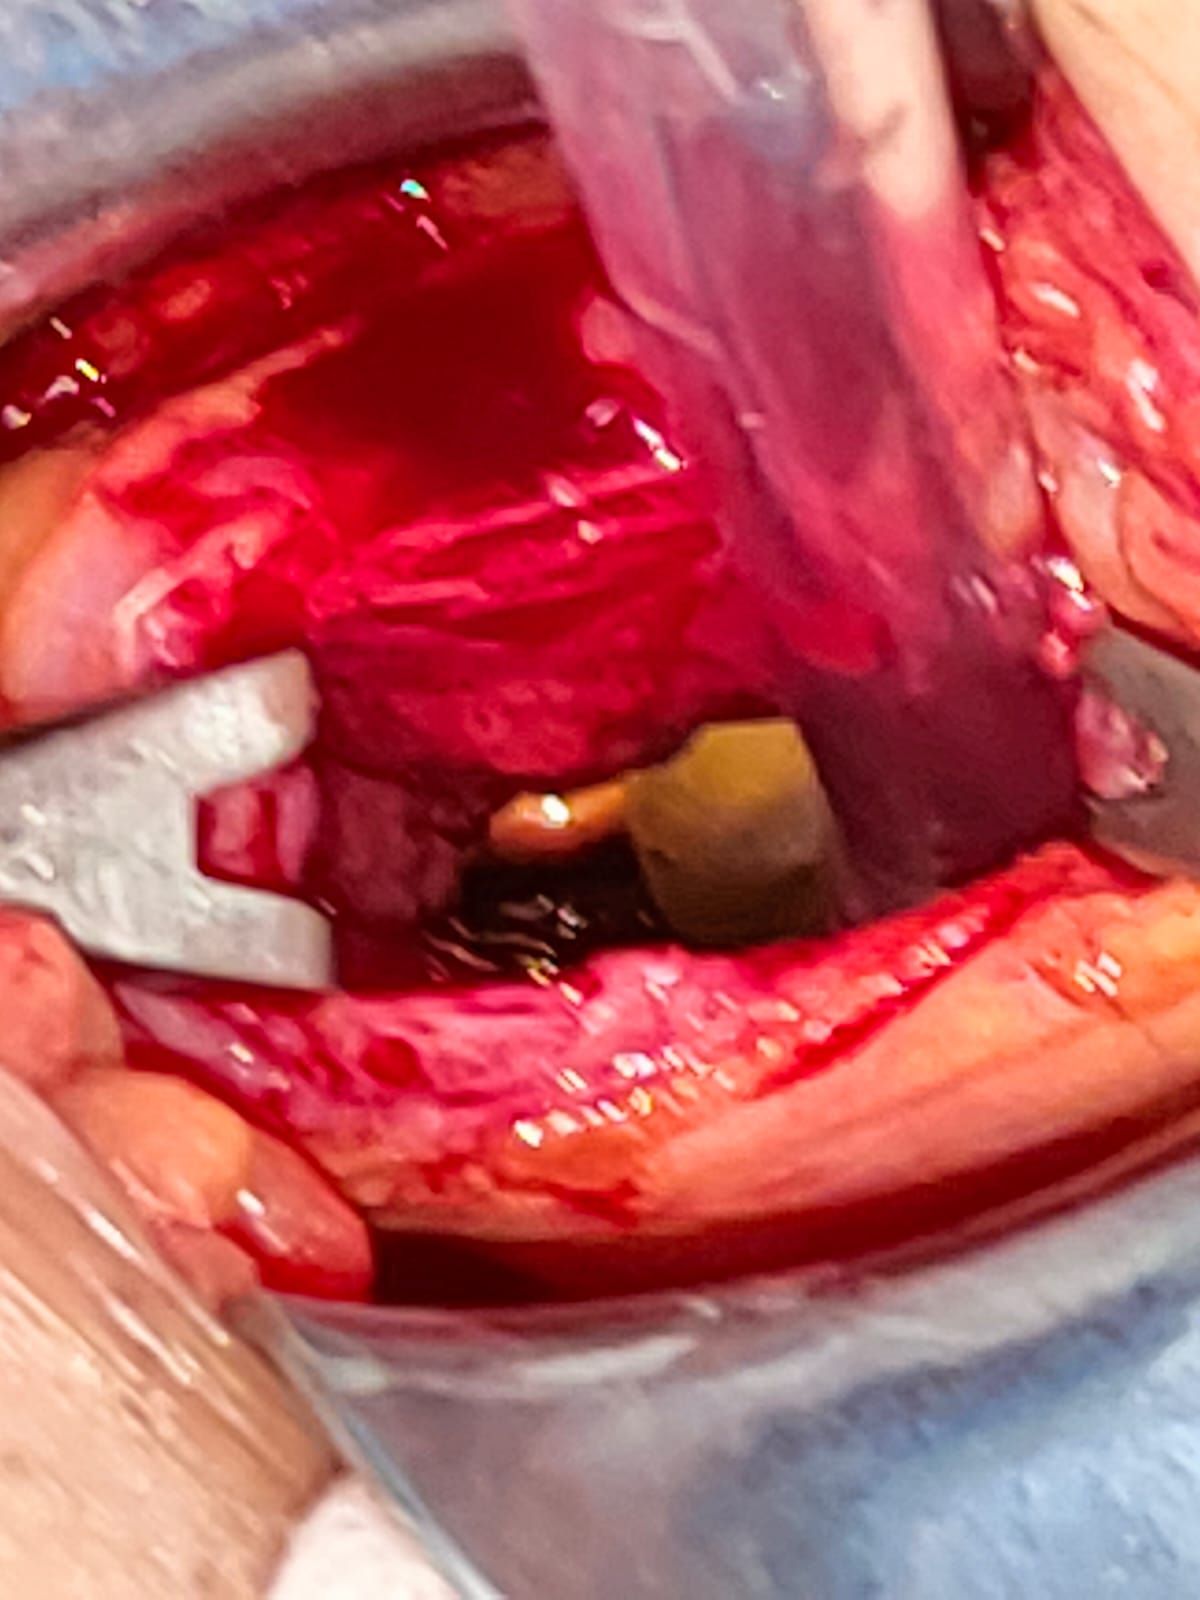

Mi experiencia abarca un espectro diverso, desde apendicitis hasta afecciones de la vesícula biliar, el colon y el recto. Como especialista en Laparoscopia, estoy dedicado a utilizar técnicas avanzadas y soluciones personalizadas para abordar las necesidades únicas de cada paciente.

• Cirugía de vesícula y vía biliar

• Apendicectomia por laparoscopia